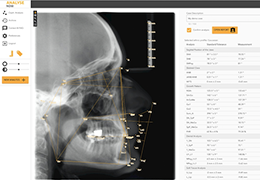

成像智能。

Eclipse 成像智能功能提供强大的处理能力和最佳质量的影像,同时减少质量错误并提高剂量效率。

凭借 AI、专有算法和先进的影像处理能力,提供出色的影像质量和无与伦比的诊断信心。